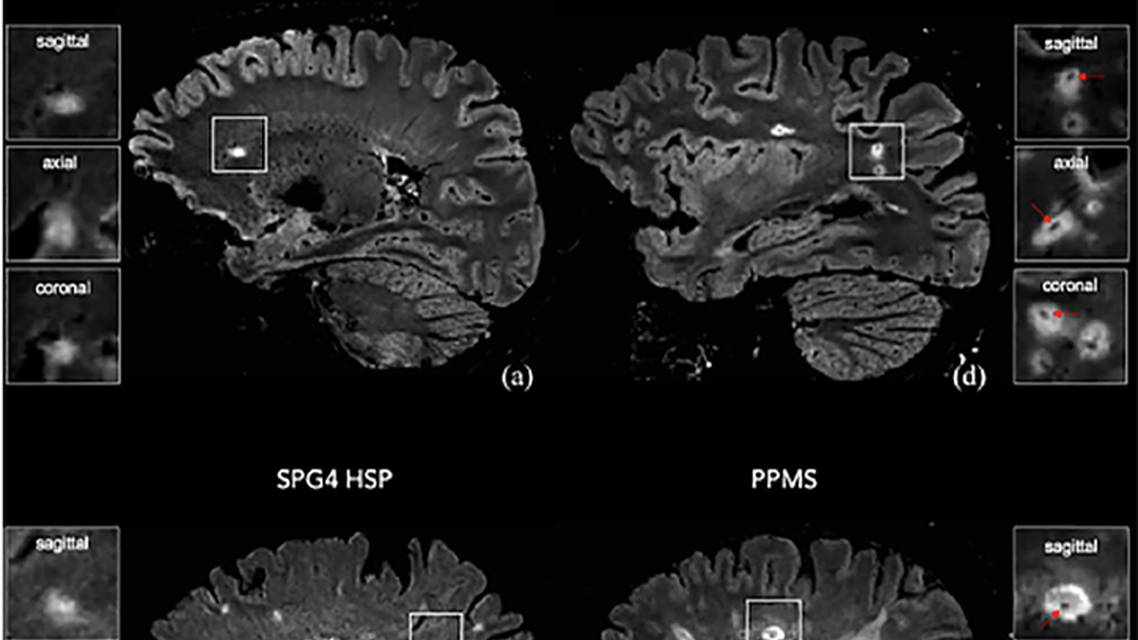

Early histopathologic studies reported that most demyelinating lesions are centered on small parenchymal veins and this is confirmed by high-field MRI (3T and 7T) using T2-weighted sequences. The central vein sign (CVS), refers to a vein visualized inside a white matter lesion on T2 MRI sequences that appears as a hypointensity relative to the surrounding lesion. The vein appears as a dot or thin line that is located centrally, running partially or entirely through the lesion. The CVS has been observed in all clinical phenotypes of MS, including relapsing and progressive forms of the condition. The CVS has been proposed as an imaging biomarker of great diagnostic value for distinguishing between MS and MS mimics. Studies have examined the presence or absence of central vein sign in nonMS pathology, including inflammatory vasculopathies, neuromyelitis optica spectrum disorder (NMOSD), and small vessel disease (SVD) (Figure). The current understanding is that the presence of a CVS can accurately differentiate MS from similar nonMS pathology provided a minimal cut-off between 40% to 50% of lesions with the CVS is reached.10